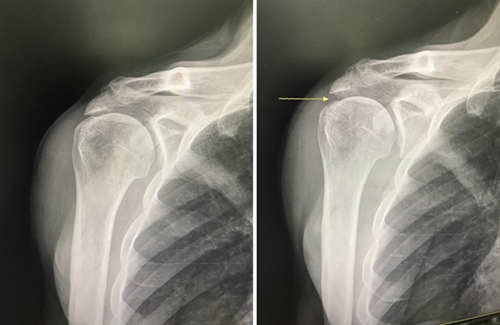

¡ã (ÁÂ) ȸÀü±Ù°³ ÆÄ¿À» ¹æÄ¡ÇØ »ó¿Ï°ñ°ú °ßºÀ »çÀ̰¡ Á¼¾ÆÁ® ¿òÁ÷ÀÏ ¶§ »À³¢¸® ¸Â´ê´Â »óÅÂ, (¿ì) »ó°üÀý³¶ Àç°Ç¼ú ¼ö¼ú 6ÁÖ ÈÄ X-ray : ÆÈ»À¿Í °ßºÀ »çÀÌ¿¡ °ø°£ÀÌ »ý±ä ¸ð½À